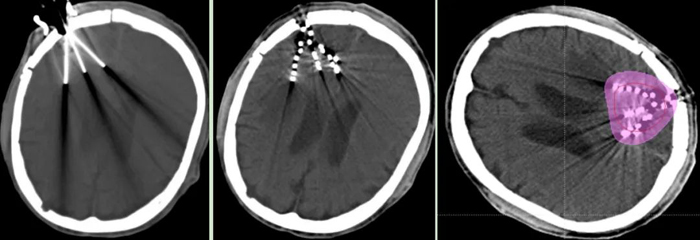

近日,我院腫瘤一科成功為一名腦膠質(zhì)母細(xì)胞瘤術(shù)后放療后復(fù)發(fā)患者,實施“CT引導(dǎo)腦部腫瘤125I放射性粒子植入術(shù)”。

經(jīng)腫瘤科、神經(jīng)外科、影像科等科室多學(xué)科討論,認(rèn)為患者無再次手術(shù)及放療指征,決定行“CT引導(dǎo)125I放射性粒子植入術(shù)”。經(jīng)周密術(shù)前準(zhǔn)備,在神經(jīng)外科吳超副主任醫(yī)師協(xié)作下,張開賢主任帶領(lǐng)粒子治療團(tuán)隊歷經(jīng)2個小時,在CT精準(zhǔn)引導(dǎo)下,成功完成了125I放射性粒子植入術(shù),現(xiàn)恢復(fù)良好。術(shù)后劑量驗證,達(dá)到術(shù)前計劃要求。